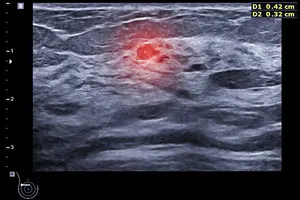

2. 초음파 검사에서 이상 소견이 발견된 경우

유방 초음파 검사를 통해 혹이나 종양이 발견된 경우, 맘모톰을 이용하여 조직을 채취하여 정확한 진단을 내릴 수 있습니다.